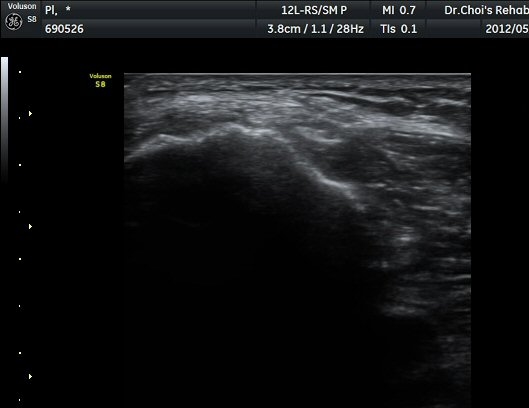

ŽÃËÁö¸¦ Á¶±Ý ´õ ¾Æ·¡·Î À̵¿ÇÏ´Ï »ÀÀÇ µÎ²²°¡ °¨¼ÒÇÏ´Â °ÍÀ» º¸°í ºñ°ñÀÇ ¸ñ ºÎÀ§¸¦ °üÂûÇϰí ÀÖÀ½À» ¾Ë ¼ö ÀÖ°í ÃѺñ°ñ ½Å°æÀº ºñ°ñ ¸ñ Ç¥Ãþ¿¡¼­ °üÂûµÈ´Ù(±×¸² 5).